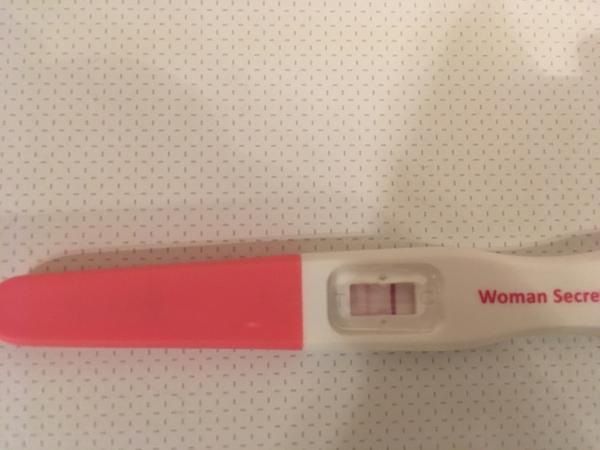

- Na identifikáciu plodných dní ženy v diskusii bežne používajú ovulačné testy (spomenuté značky Pepino, Rapiclear, Women secrest) a testujú denne alebo aj 2× denne, pričom niektoré uviedli testovanie v rozsahu ~10–16 DPO.

A: Ženy používali ovulačné testy denne alebo aj 2× denne a spomínali značky Pepino, Rapiclear a Women secrest; niektoré uviedli, že ovu test ukázal „silnú“ líniu predtým, než sa objavil pozitívny tehotenský test.

aj ja tam vidim druhu carocku, tak doufam ze bude kazdym dnem silnejsi a pak uz jen doktor ukaze pekny obrazek. 🙂

@tamarka9 dakujem zlatik 😉 no vcera ma @alilka pod hrozbou nasilia donutila urobit test 😂😂😂 som chcela az dnes. Dufam ze bude silniet. Zajtra rano urobim dalsi. A ano mame uz synceka krasneho. To je zazrak ze tie vitaminy tak zabrali. Myslim ze hlavne nosifol pomohol. Kazdej odporucam co ma problem s kvalitou. Aj ked zistit sa to da az odberom pri ivf. No je to zazrak. Strasne ma boleli stehna a krize take 4 dni, tak som v kutiku duse dufala ☺

@montblanc Aaaaano, vidím slabé čiarky, vyzerá, že sa zadarilo 🙂 gratulujem